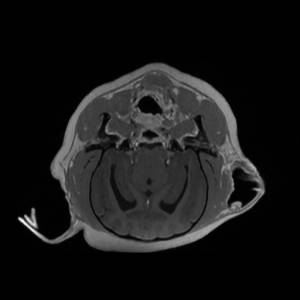

Main Gallery

Playing with a photo gallery function. It is possible to have multiple galleries, each within a namespace.